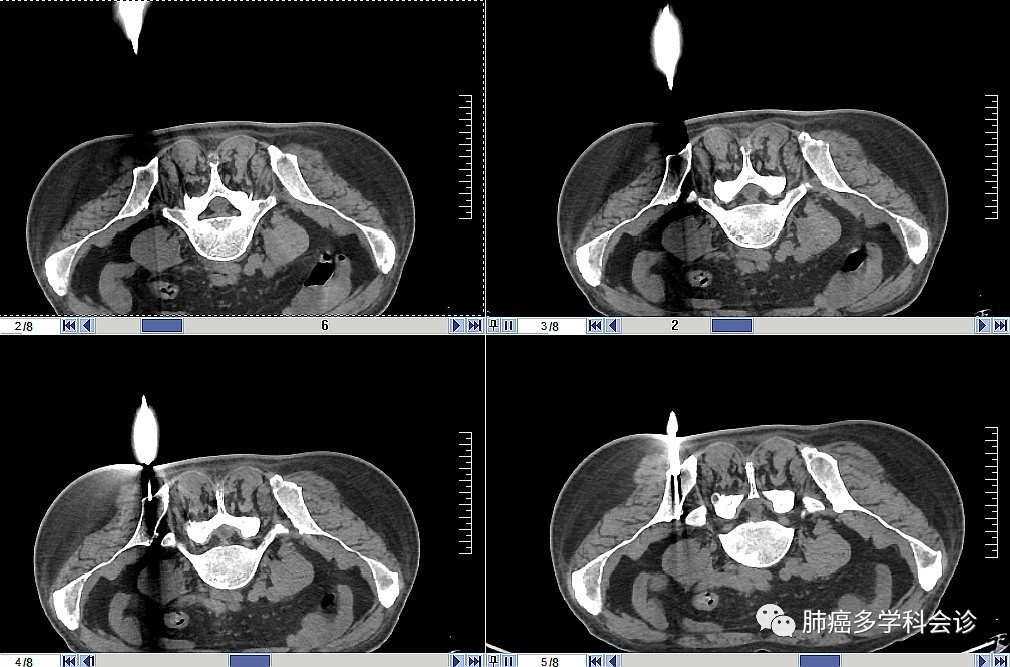

以下是患者的PET-CT图像: